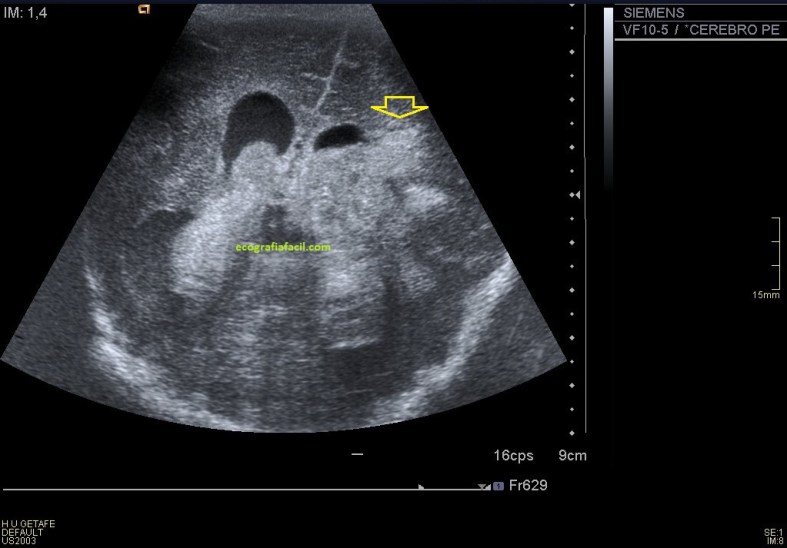

Asociado a esta masa, descendiendo por el canal inguinal, en la búsqueda del teste, encontramos un área donde unas estructuras tubulares y tortuosas de aspecto anecoico y móvil muy compatibles con varicocele, que ya hemos estudiado en el blog con anterioridad y compatibles con venas varicosas…

…con la aplicación del doppler color y la maniobra de valsalva confirmamos dicha sospecha para que el radiólogo tenga constancia del hallazgo. Marcamos siempre la maniobra, y colocamos siempre correctamente el pictograma como indica la flecha amarilla, recuerda que no solo la calidad de imagen debe ser el objetivo. El TSID trabaja para un radiólogo que revisará la imagen eco-anatómica y toda la información que nosotros podamos ofrecerle al margen usando textos y/o pictogramas en el contexto siempre de un protocolo como el que estoy contándote hoy.